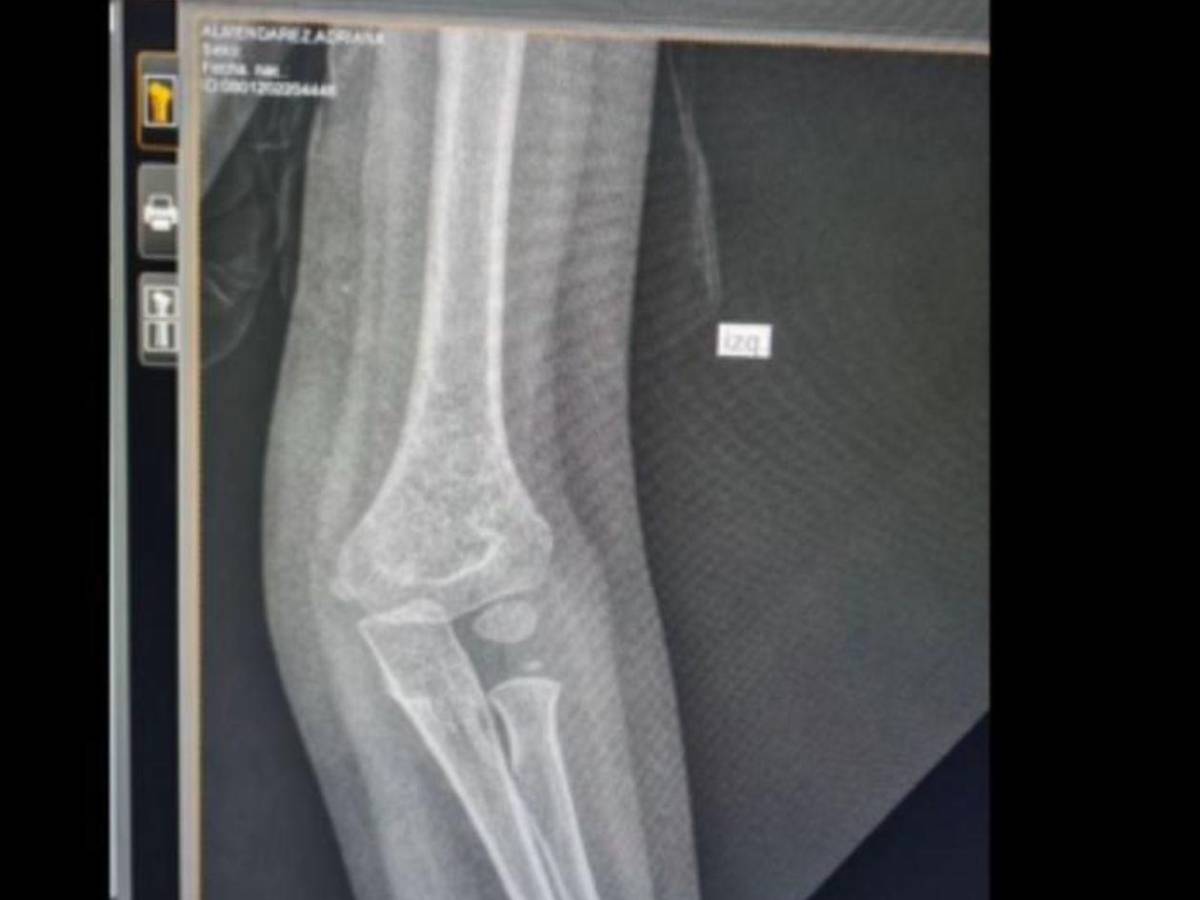

Según Espinal, al momento de realizarle los exámenes a la menor, los médicos le informaron que no había placas para radiografías. Ante esa situación, ella tuvo que improvisar: “Mi hija se fracturó el codo y tuve que tomarle foto al examen con el celular para mostrársela al doctor”.